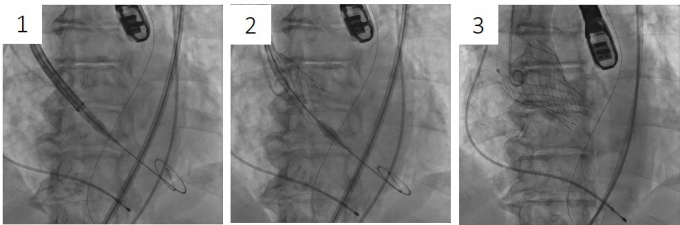

2. 自己拡張型人工弁

(1)カテーテル内に小さく収納した人工弁を弁輪部に配置し、(2)緩徐な展開により、(3)適正な位置に拡張留置します。